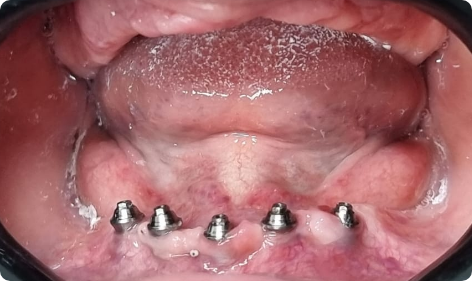

Muitas vezes é possível realizar em carga imediata, que consiste em apenas uma etapa a colocação dos implantes, que são os parafusos de titânio e a instalação da prótese.

Caso não seja possível a realização da carga imediata, o paciente passará por duas etapas. A primeira é a etapa cirúrgica para a colocação dos implantes e após quatro meses, a etapa protética que iniciará a confecção da prótese protocolo.